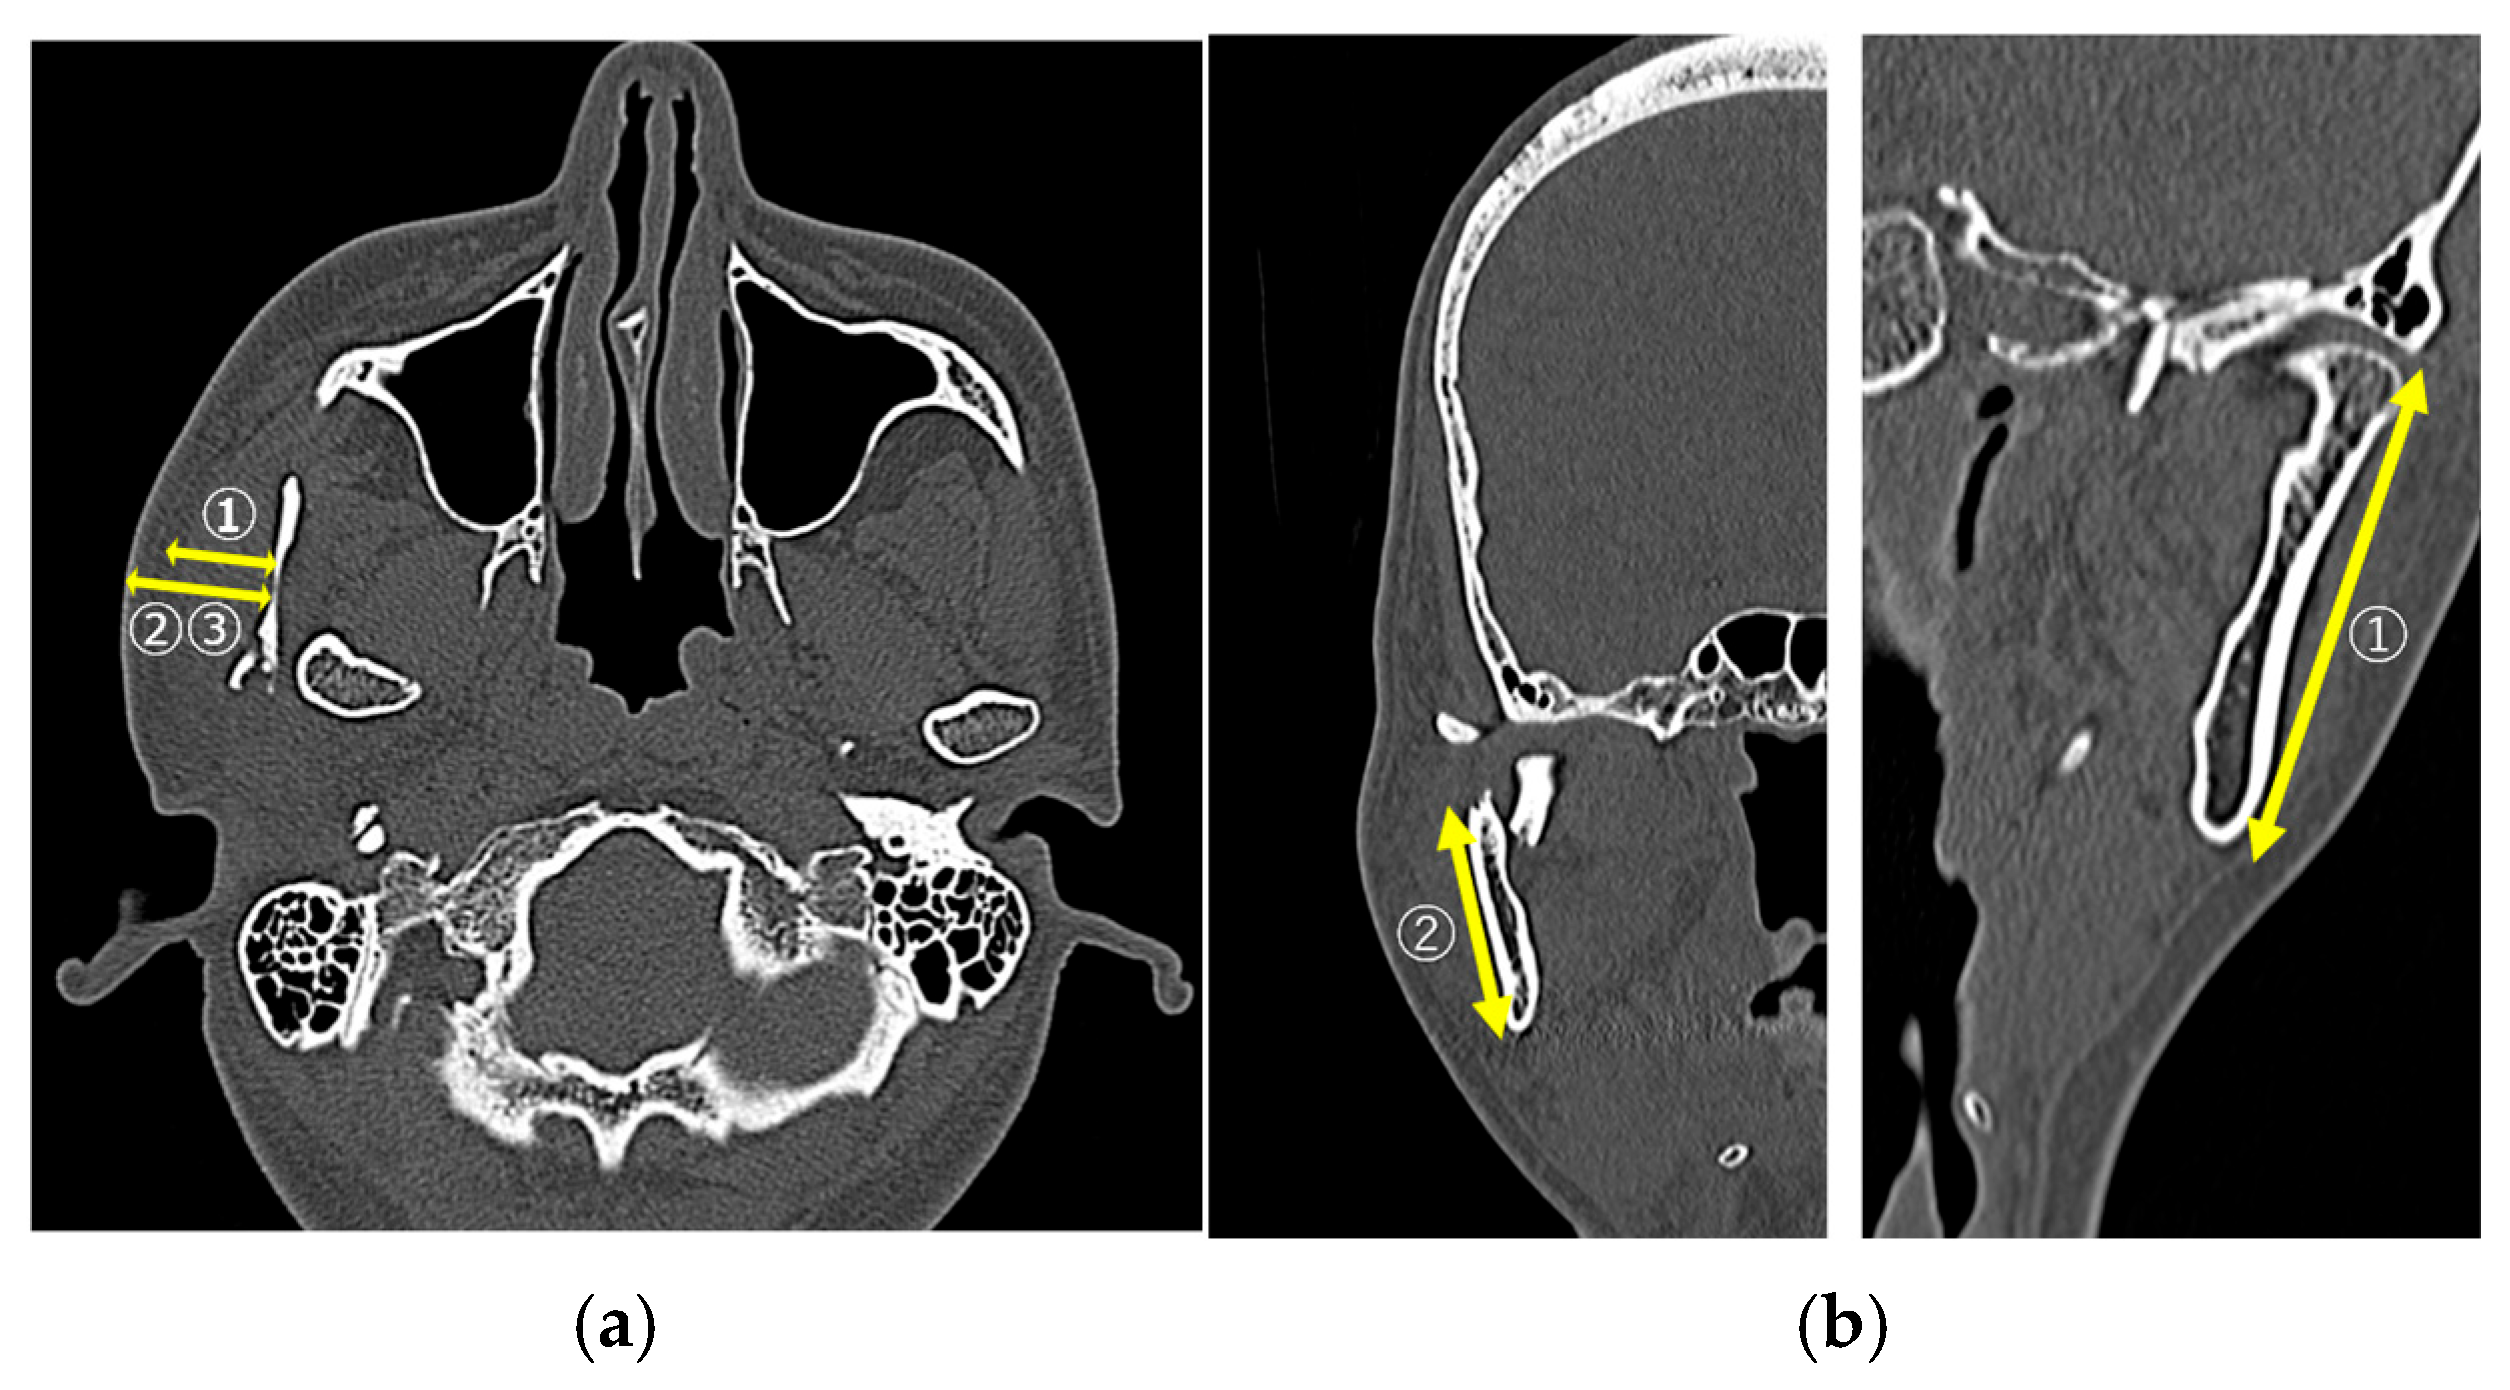

2.2.4. Data Obtained via Computed Tomography Evaluation